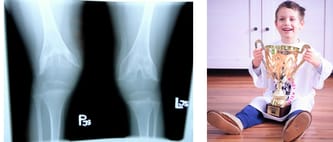

A oto Staszek i jego radość :)

27.06 odbyła się operacja Stasia. Wszytko poszło zgodnie z planem, a Staś dziękuje wszystkim, którzy mu ten własnie wspomniany plan, pomogli zrealizować!